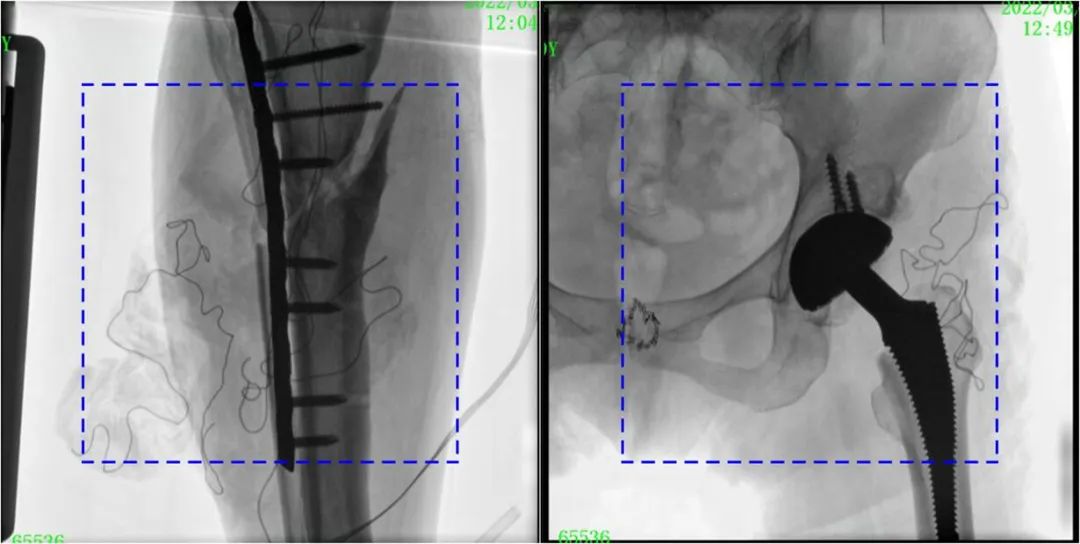

術(shù)中定位準確、出血量少,術(shù)后影像顯示股骨移位糾正,恢復(fù)良好力線,手術(shù)效果良好。

PLX119C臨床圖像與傳統(tǒng)圖像對比

注:藍色虛線內(nèi)為傳統(tǒng)21CM×21CM平板的成像區(qū)域。